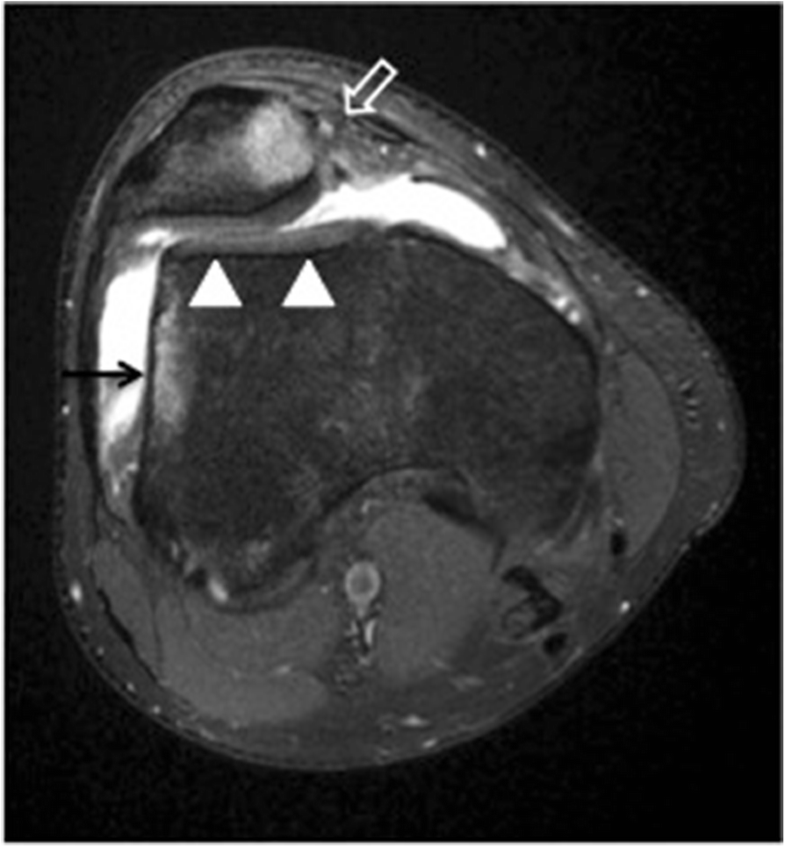

A 25yearold active male patient with patellar maltracking and What Does Patellar Maltracking Mean The most common form is rotational malalignment, whereby the patella is tilted, lateral side down. Patellar maltracking is a disorder that often affects the young active individuals. Learn about the common factors, signs, and conservative options for this condition from idaho. Patellar maltracking is a disorder of the patellofemoral joint caused by imbalance of the dynamic relationship between the patella. What Does Patellar Maltracking Mean.